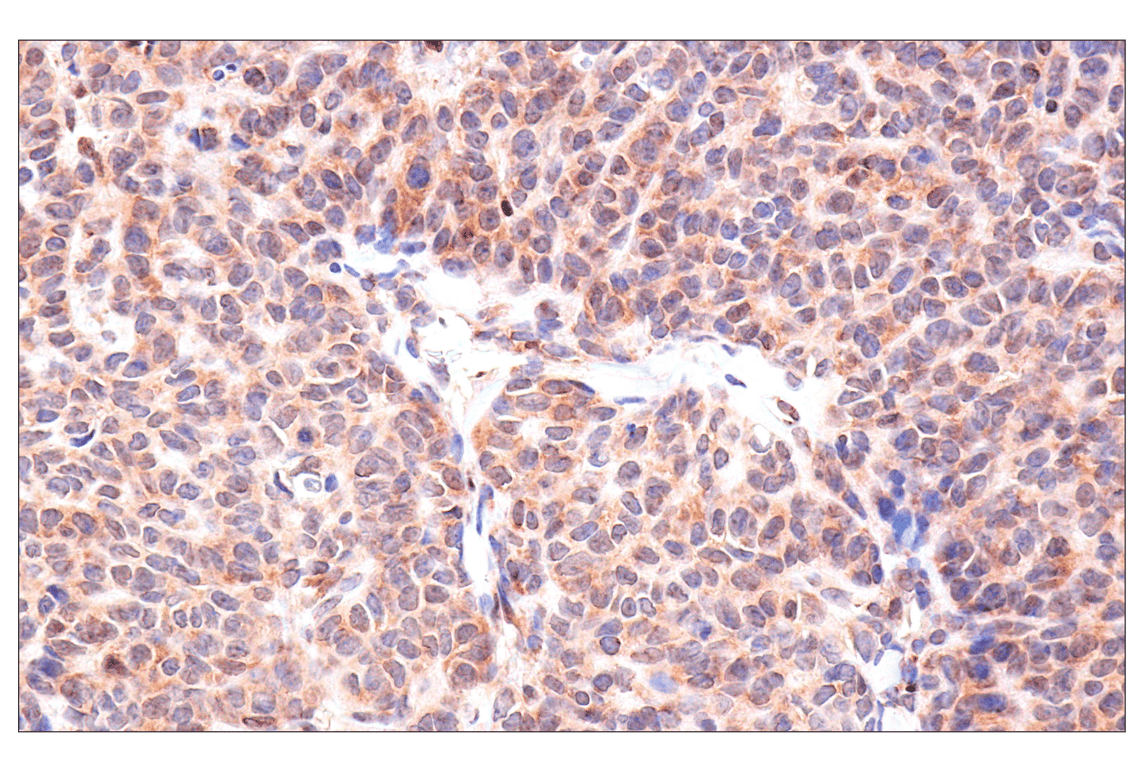

Immunohistochemical analysis of paraffin-embedded human endometrioid adenocarcinoma using ADAR1 p150 Isoform (E6U1U) Rabbit mAb.

Immunohistochemistry Image 1: ADAR1 p150 Isoform (E6U1U) Rabbit Monoclonal Antibody